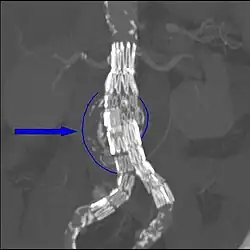

- Die Angiographie kann Aneurysmata nur bedingt zur Darstellung bringen, da sich das Kontrastmittel nur in durchströmten Anteilen des Gefäßes abbildet. Sie ist aber sehr gut geeignet, eventuelle Beteiligungen abgehender Gefäße (z. B. Nierenarterie) zu erkennen.

Die endovaskulären Prothesensysteme bestehen aus einem selbstexpandierenden Nickel-Titan (= Nitinol)-Skelett, das von einer dünnwandigen Polyester- oder PTFE-Prothese überzogen ist. Dieses System wird auch Stentgraft, Hybridprothese oder gecoverter Stent genannt. Am gebräuchlichsten und in der elektiven Situation fast ausschließlich gebraucht sind modular aufgebaute Bifurkationsprothesen. Das Hauptmodul besteht aus dem Prothesenkörper, einem langen und einem zweiten kurzen Schenkel. Letzterer wird mit einem gesonderten kontralateralen Schenkel ergänzt. Beide Komponenten sind in getrennten Entladungssystemen verpackt. Sie werden über eine Inzision der Leistenarterie eingeführt, unter Röntgendurchleuchtung in das Aneurysma platziert und expandiert. Es sind auch aorto-uni-iliakale Systeme erhältlich, bei welchen die Blutversorgung des kontralateralen Beines über einen Crossover-Bypass erfolgt. Postinterventionell kann der Patient nach einem kurzen Aufenthalt auf der Überwachungsstation auf die Normalstation verlegt werden. Die Entlassung erfolgt nach Kontrolle bezüglich Endoleak (Duplexsonografie und CT) ca. vier Tage nach der Operation. Im Gegensatz zur offenen Operation, bei welcher kaum Nachkontrollen nötig sind, liegt das große Problem der Endoprothesen in der Entwicklung von so genannten Endoleaks (Leckage), die in bis zu 44 % der Fälle auftreten. Durch Endoleaks kommt der Aneurysmasack wieder unter systemischen Blutdruck, so dass das Ziel der Operation nicht erreicht ist. Folgende Endoleaktypen werden unterschieden:[2]